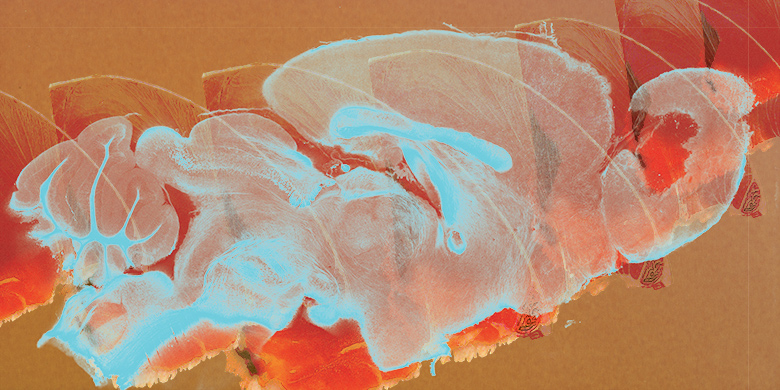

WAVES

Scientist Collaborator Allison Yukiko Louie

Andrew Steelman Laboratory

Zeiss 710 Multiphoton Confocal Microscope

Funded by the United States Department of Agriculture, University of Illinois at Urbana–Champaign start-up funds and the National Multiple Sclerosis Society Pilot Research Grant

Myelination is an important process in the brain where a fatty substance called myelin is formed around axons of neurons. The formation of myelin increases the speed of electrical signals traveling along the axons, thus playing a vital role in the central nervous system. Researchers are investigating the effects of diet and disease on myelination processes using mouse brains.

A tissue-clearing technique called CLARITY (Clear Lipid-exchanged Acrylamide-hybridized Rigid Imaging/ Immunostainingcompatible Tissue-hYdrogel) was used to render the brain tissue transparent while maintaining an intact protein scaffold. The image, taken with a confocal microscope, shows a sagittal section of the mouse brain immunostained with anti-proteolipid protein. This piece conveys the fragile yet complex nature of the brain.